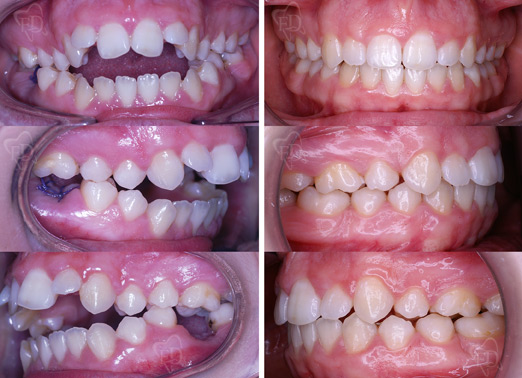

Malocclusione II classe senza estrazioni:

prima dopo

Malocclusione III classe agenesia incisivi laterali: